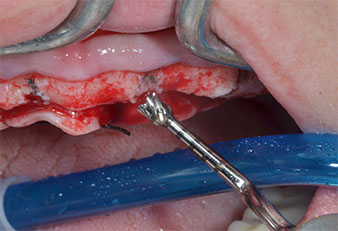

Un insert piézoélectrique diamanté de forme effilée (Piezomed I1) a été utilisé pour marquer les positions implantaires et effectuer la préparation pilote (Fig. 3). On a pris soin de travailler selon un mouvement ascendant et descendant, à puissance réduite, irrigation complète et basse pression (moins de 300g). Ensuite, un insert pilote (Piezomed I2A/I2P) a été utilisé pour l’agrandissement initial de 2mm du diamètre des sites implantaires (Fig. 4), suivi d’un insert de 3mm (Fig. 5).